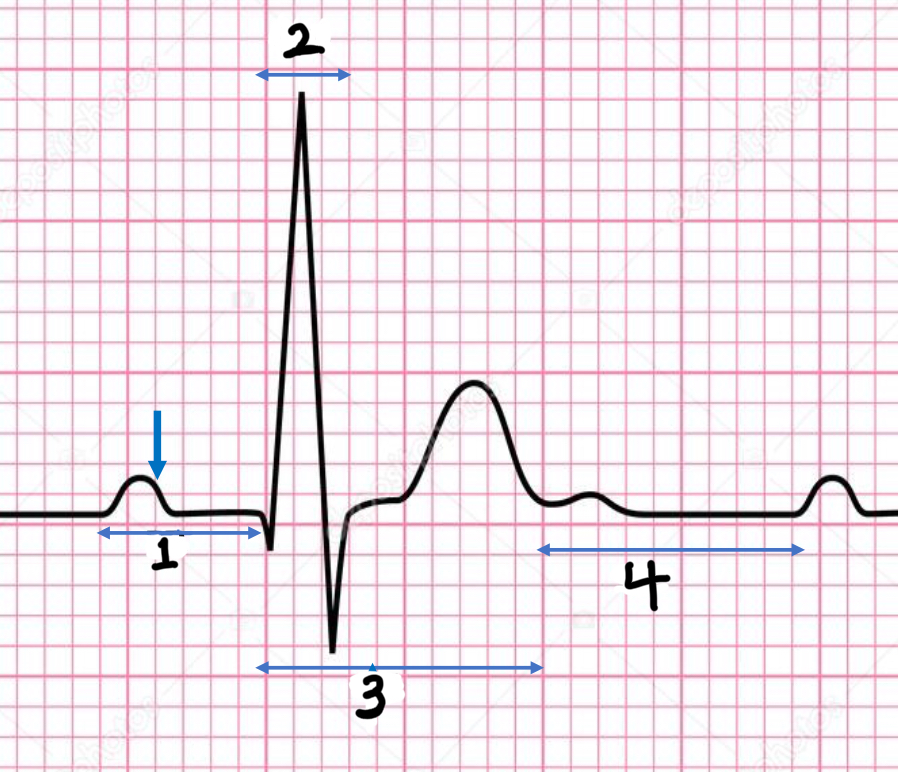

P wave

atrial depolarization

Precedes atrial contraction

QRS complex

ventricular depolarization

Precedes ventricular contraction

T wave

ventricular repolarization

PR interval

Name #1

QRS interval

Name #2

QT interval

Name #3

TP interval

Name #4

PR interval

time from beginning of the P wave to the beginning of the QRS complex

QRS interval

Time from beginning of the QRS complex to the end of the QRS complex

QT interval

Time from beginning of QRS complex to the end of the T wave

TP interval

Time from end of T wave to the beginning of P wave

RR interval

Distance from the peak of one R wave to the peak of the next

0.04

The x axis is time in seconds.

1 mm equals……. seconds?

0.1

The y axis is voltage in mV.

1mm equals ….. mV?

HR = 1500/x mm

Equation for HR or bpm